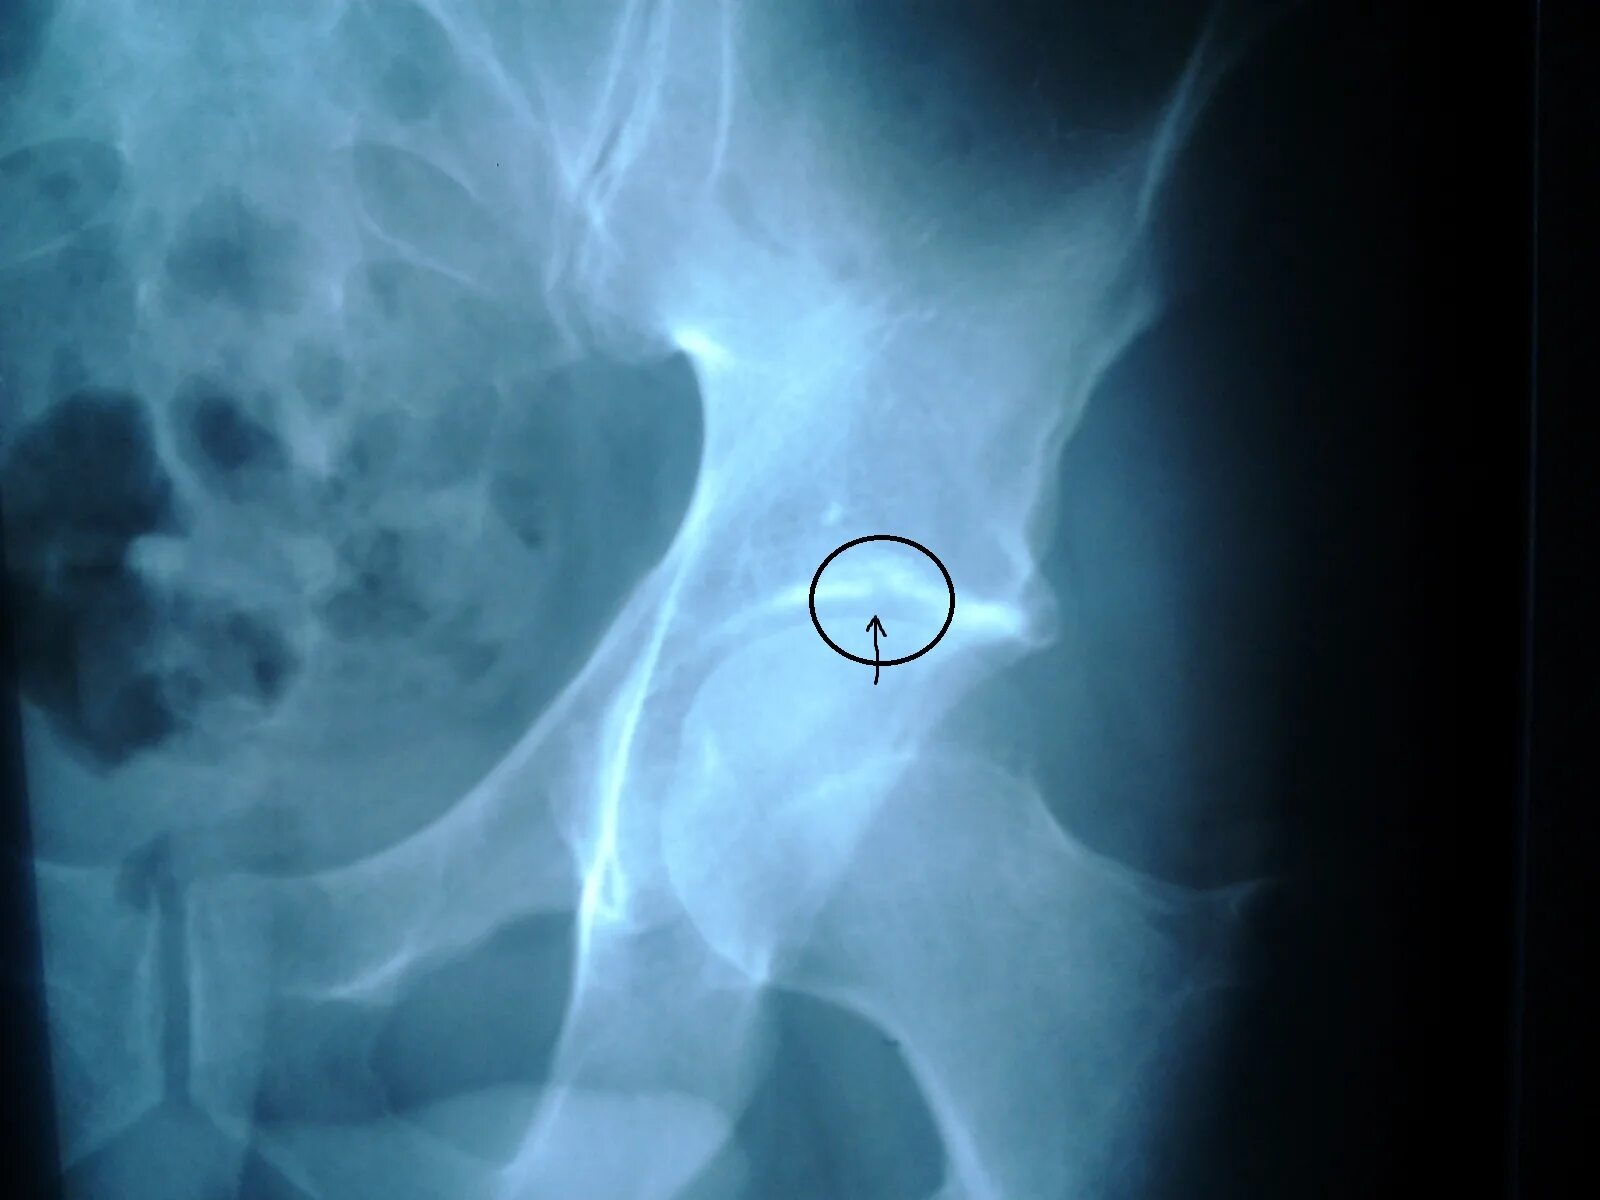

Склероз вертлужной впадины